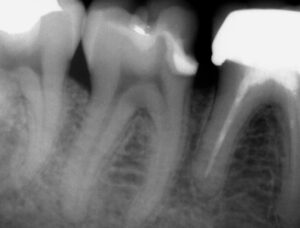

Were you told a cavity is too deep to fix? Using Microscopic Deep Margin Elevation and Dual-Laser Technology, we preserve your natural tooth structure and avoid aggressive extractions.

Traditional dentistry often requires painful surgery (Crown Lengthening) to reach decay below the gumline. Our DME Protocol is a non-surgical alternative. We “elevate” the floor of your cavity using bioactive materials, keeping your tooth intact and your gums health